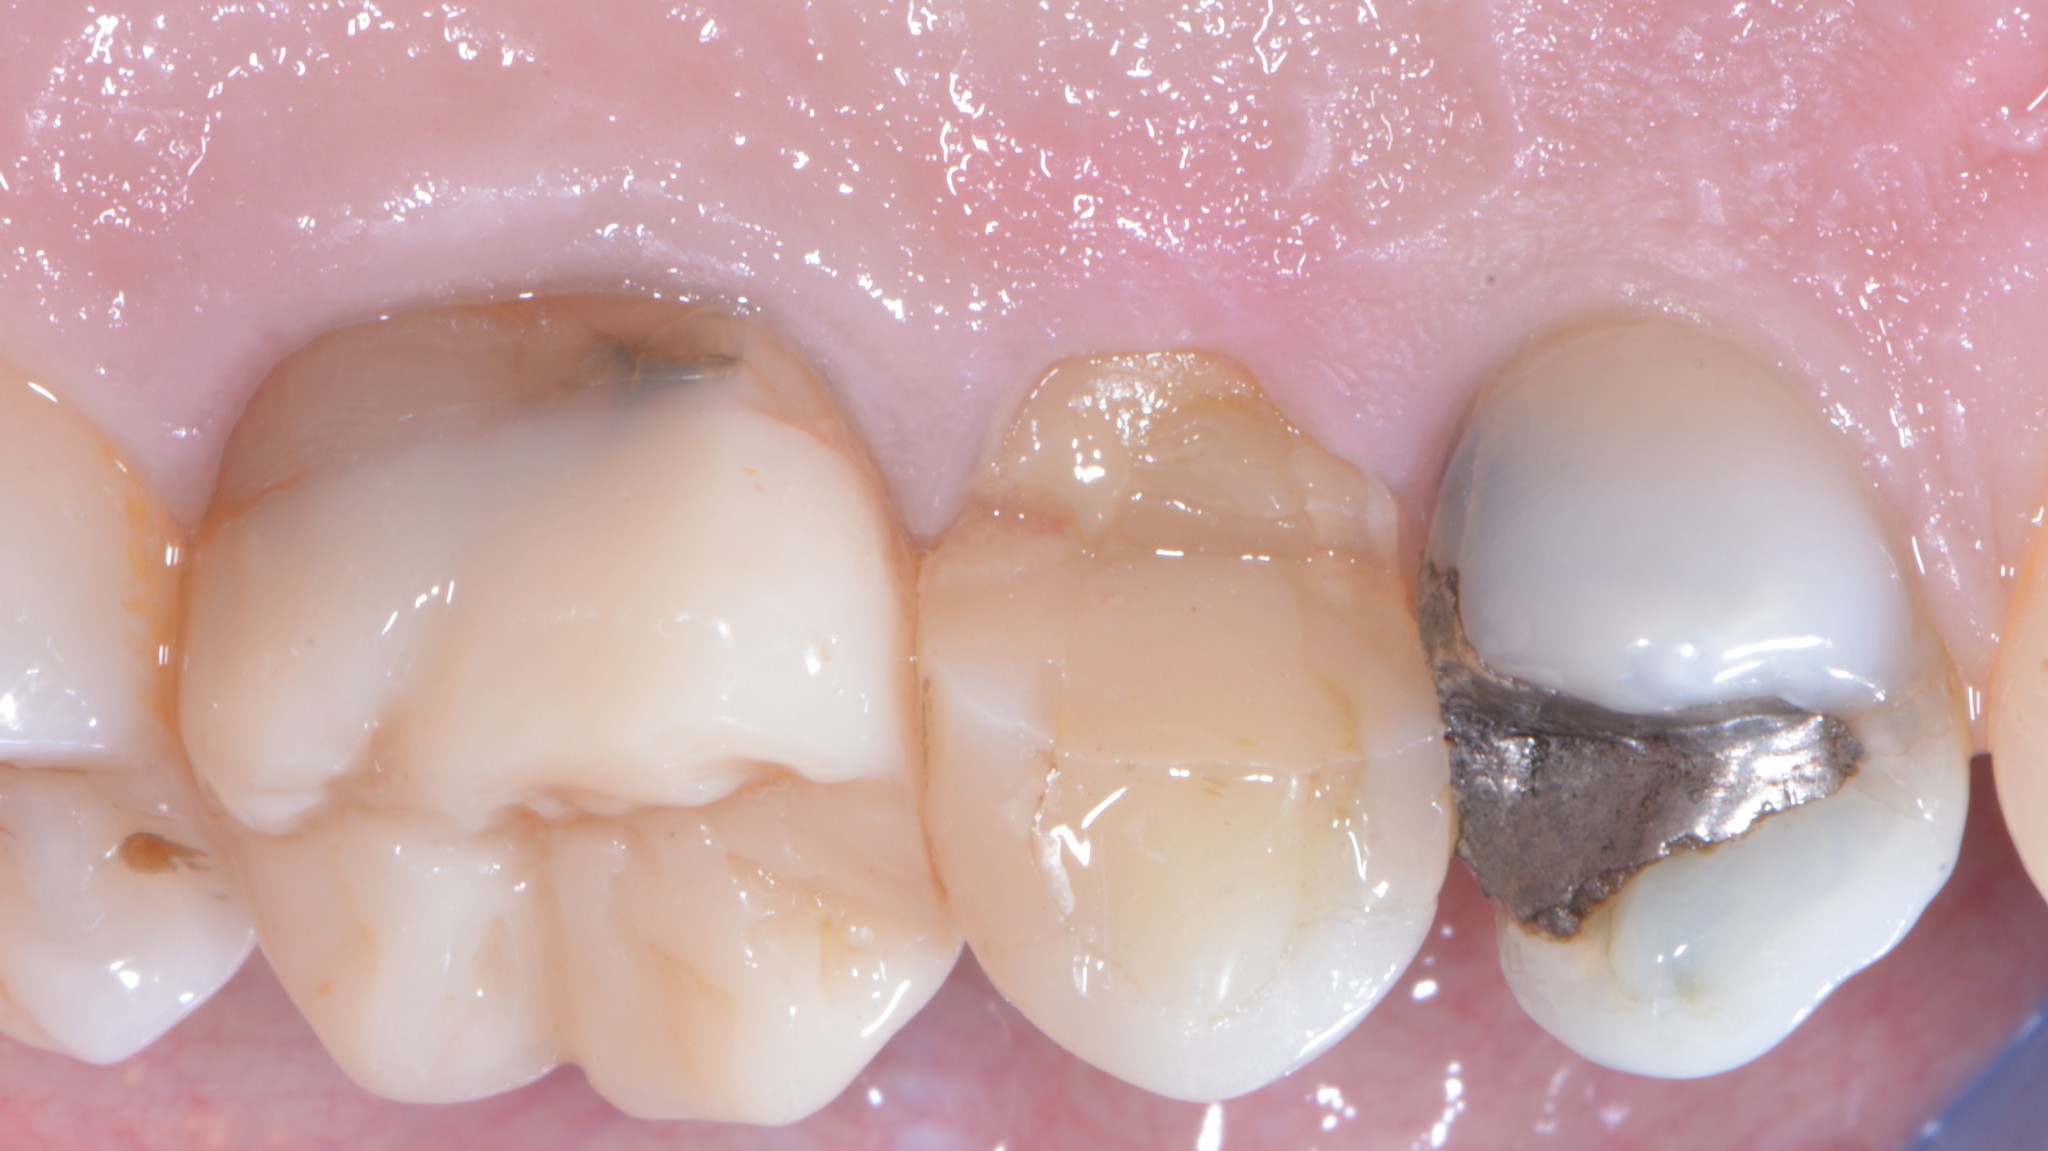

Spesso capita che i premolari e i molari superiori si fratturino dal lato palatino. In questi casi possiamo eseguire un allungamento che si limita a quell’aspetto in modo da preservare l’estetica vestibolare pur mantenendo l’imprescindibile condizione di un’anatomia positiva della festonatura gengivale.

Eccoti un video totalmente gratuito che spiega questa tecnica.